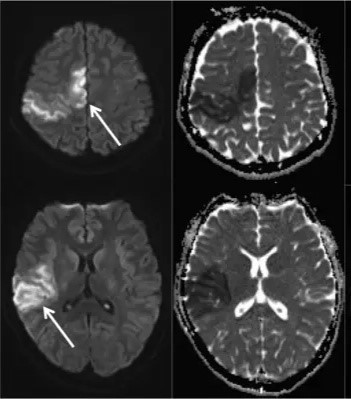

医院急诊CT未见异常,头部MRI提示右侧大脑中、大脑前动脉供血区域弥散受限(见下图)。